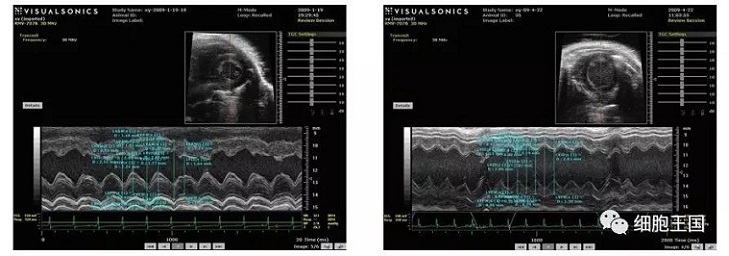

干細胞移植后各臟器呈現較之前狀態,具體表現在以下幾個方面(如圖)。

超聲心動圖顯示對照組左室舒張期容積低于移植組